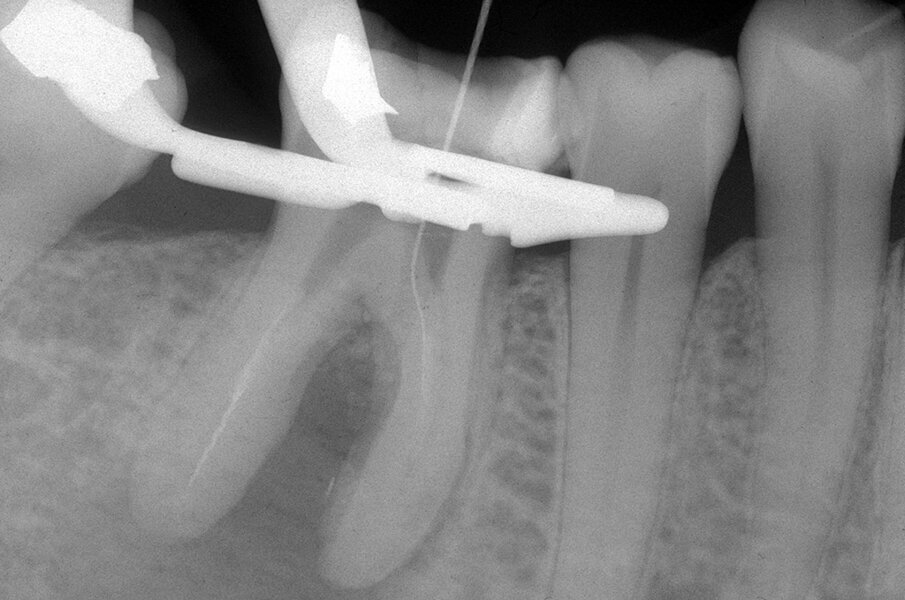

Le perforazioni del terzo medio avvengono nella maggior parte dei casi durante la preparazione della cavità d’accesso o, più spesso, durante le fasi di detersione e sagomatura o infine durante la preparazione dello spazio per un perno con l’utilizzo di frese tipo Largo, Peeso, Gates Glidden o simili (Figg. 2a-2f).